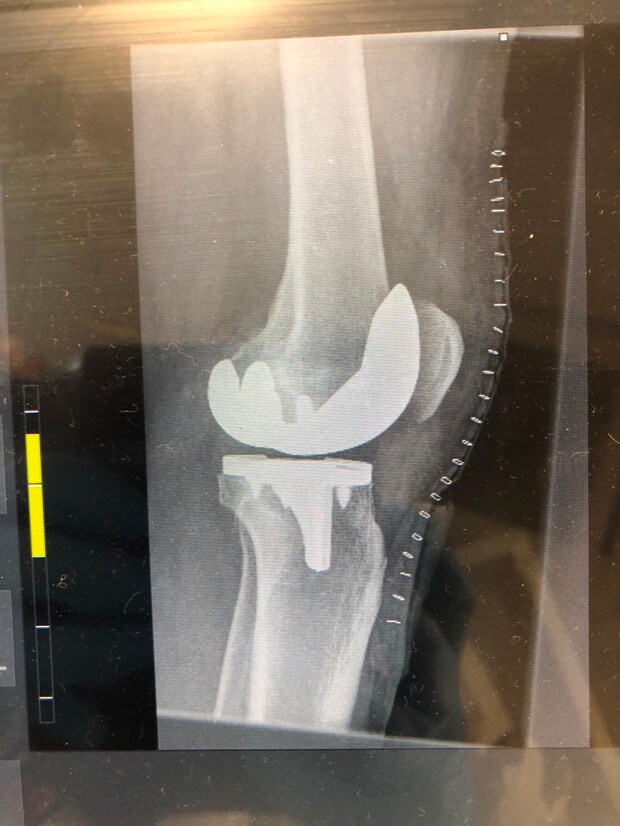

3. Stephen, I've been there - I've got similar X-rays, though mine have random bits of metal from earlier ACL's. Right knee for me. Right knee is "better" as the loading through the swing is more intense on the left knee for right handers. One week in can be a low point. No point in being a hero - take whatever painkillers they give you!! Stairs will be an issue for some considerable time I'm afraid. You will, however, be able to use stairs to strengthen your muscles. Be diligent about your physio and to get access to an exercise bike of some description! When allowed, I did lots of walking and found it helped. I had my op in the November and was ready for the Driving Range the following March. Some say they were back on the golf course six weeks after the op - I would consider that to be a very risky strategy. It's a major reconstruction and it takes time to heal. The numbness wears off eventually but don't expect it to be exactly like a natural knee - it's good, but it's not that good! Oh, and be prepared to be stopped by Security at every airport - You'll set of the metal detector alarms!!